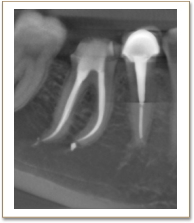

歯根の先端の病巣発見や、治療後の治癒の状態など、かなり正確に把握できます。

歯科用CT画像を使った正確な診断によって、根の病気の完治を目指しやすくなります。